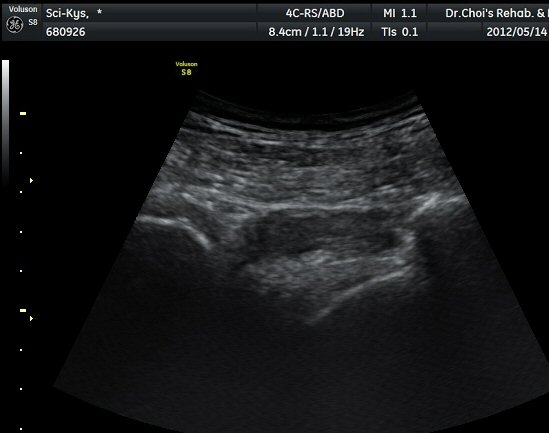

¾ûµ¢ÀÌ Á°ñ¿¡¼­ Á°ñ½Å°æ Ⱦ´Ü¸é°Ë»ç¿¡¼­ ´ëµÐ±Ù°ú quadratus femoris »çÀÌÀÇ ±Ù¸·

°æ°èºÎ¿¡¼­ Á°ñ½Å°æÀÌ °üÂûµÇ´Âµ¥ ³»Ãø Á°ñ°áÀý(ischial tuberosity) ÃøÀ¸·Î Ä¡¿ìÃÄ

ÀÖ´Â °ÍÀ¸·Î ÆÇ´ÜµÈ´Ù(±×¸² 1, 2, 3).